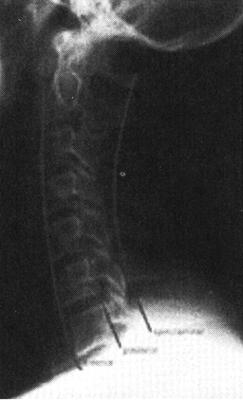

(二)脊髓造影

脊髓造影是一种有创伤性的检查,利用穿刺针向蛛网膜下腔内注入阳性造影剂使蛛网膜下腔和脊髓显影,从而了解脊髓受压情况和蛛网膜下腔的通畅情况。脊髓造影所用的造影剂为硬膜囊内注射专用碘造影剂,常用等渗非离子水溶性碘造影剂,其毒副作用小,很少产生过敏反应并且显影效果好。因而,脊髓造影仍然可作为了解脊髓病变的一种有效、安全的影像学检查方法,尤其对目前没有MRI设备的医院,脊髓造影仍然是了解椎管内病变的一种有效的检查方法(图7-3)。

图7-3 T12椎体压缩性骨折呈楔状改变,并向后突。脊髓造影显示,该水平蛛网膜下腔受压闭塞,呈双峰状